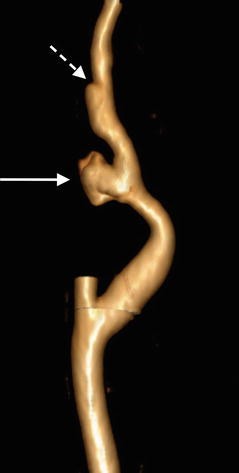

3D volumetric CTA image of the internal carotid artery with external carotid artery branches removed reveals irregular contour of the ICA pseudoaneurysm (arrow). More distally, ICA dissection manifests as focal contour abnormality of the vessel (dashed arrow)